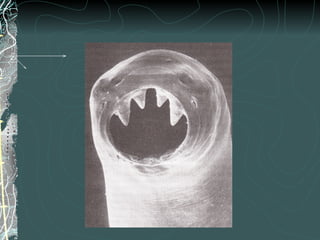

Ancylostoma duodenale

Necator americanus

Ejemplares adultos